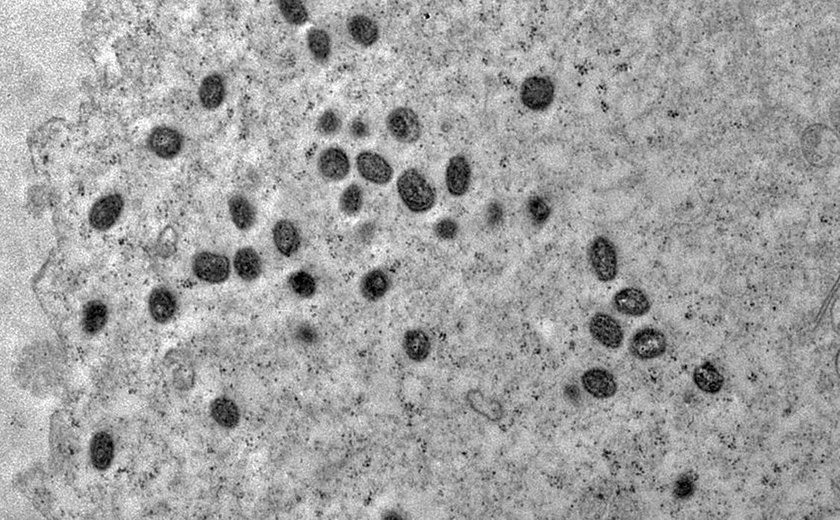

Uma pesquisa internacional, com a participação do Instituto Nacional de Infectologia Evandro Chagas (INI), da Fundação Oswaldo Cruz (Fiocruz), indicou a necessidade de se avaliar a inclusão das formas graves de monkeypox como uma nova condição definidora de Aids nas classificações das doenças do HIV no Centers for Disease Control and Prevention (CDC) dos Estados Unidos e na Organização Mundial de Saúde (OMS).

O trabalho foi feito por pesquisadores de 19 países, entre os quais Estados Unidos, Espanha, México, Reino Unido e Brasil. Eles reuniram dados de casos confirmados de monkeypox (Mpox, também chamada de varíola dos macacos) entre 11 de maio de 2022 e 18 de janeiro de 2023, para estudo que avaliou casos em pessoas com infecção avançada por HIV . O INI/Fiocruz, que é a referência para o atendimento de casos de Mpox no Rio de Janeiro, desenvolve pesquisas que contribuem para o enfrentamento dessa doença.

O trabalho destacou a descrição de uma forma grave de monkeypox, caracterizada por lesões cutâneas e mucosas necrotizantes, com alta prevalência de manifestações dermatológicas e sistêmicas fulminantes e morte, em pacientes com doença avançada pelo HIV, caracterizada por contagens de linfócitos TCD4+ abaixo de 200 células/mm3. O estudo contou com a colaboração da infectologista do Laboratório de Pesquisa Clínica em IST e Aids do INI/Fiocruz Mayara Secco Torres Silva.